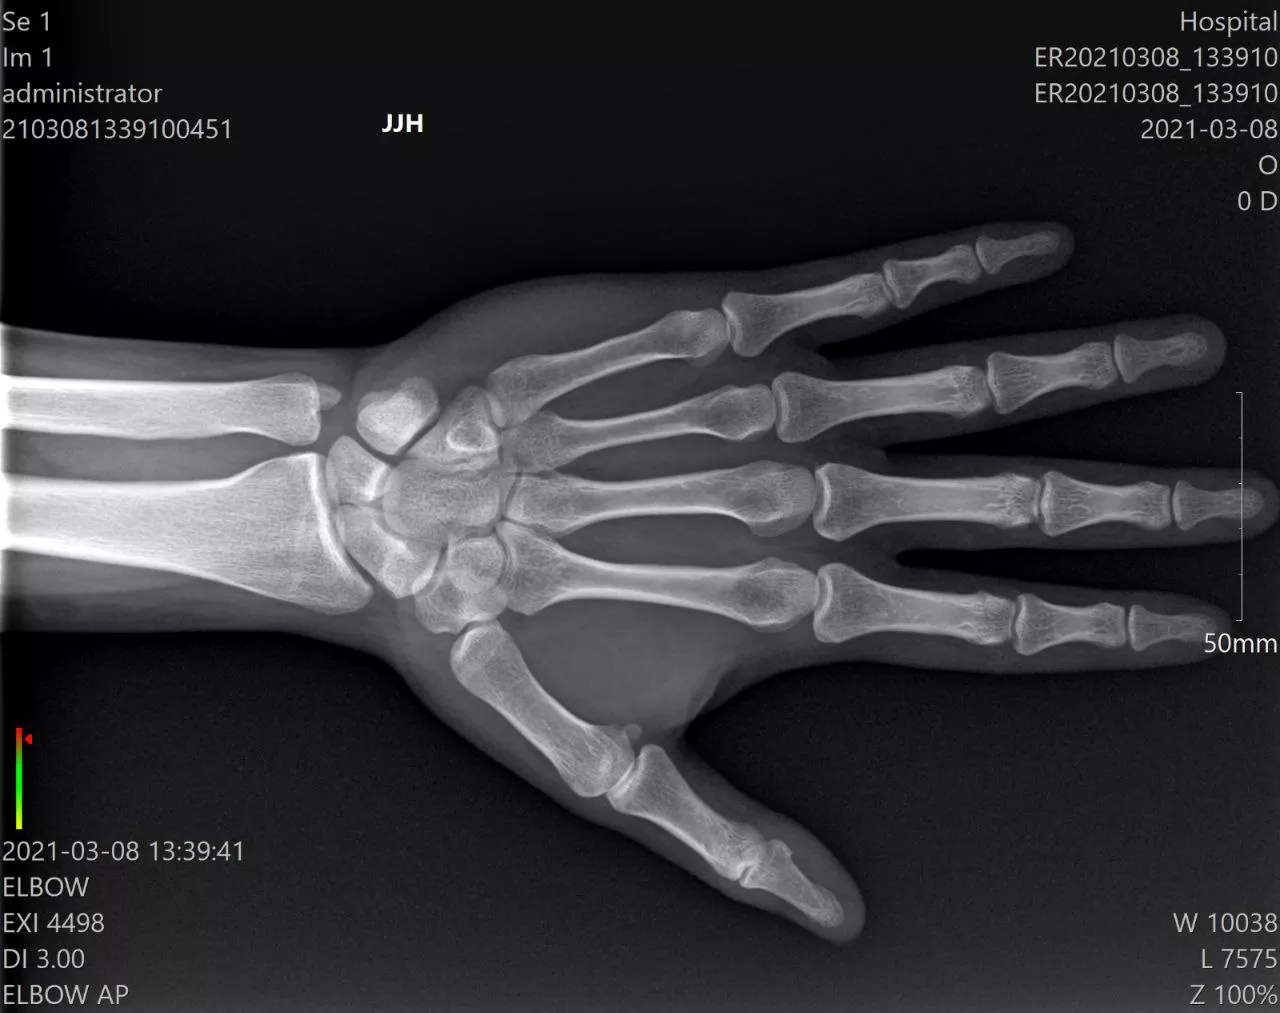

The MINE ALNU (Nooka) represents the pinnacle of portable digital radiography technology. This cutting-edge handheld X-ray system is engineered to revolutionize diagnostic imaging for modern healthcare professionals. Specifically, it empowers specialists in orthopedics, sports medicine, podiatry, and veterinary care to capture high-resolution images in any setting. It is, without a doubt, the smarter choice for on-the-go diagnostics.

In addition, the system features the renowned Mine Alnu X-ray generator, which is globally recognized for its consistent and reliable output. Paired with advanced LG detector technology, the Nooka delivers exceptionally crisp and clear images. You can choose between wired or wireless configurations depending on your specific clinical needs. Specifically, this integration ensures maximum diagnostic detail with minimal patient exposure.

- High-Resolution Imaging: Produces exceptional image quality with superior detail resolution

- Versatile Power: Operates at 40–80 kV / 3 mA, suitable for orthopedics, sports medicine, podiatry, and veterinary use.

- Sports Medicine: On-field injury assessment and athlete care

- Orthopedic Surgery: Intraoperative imaging and post-surgical verification